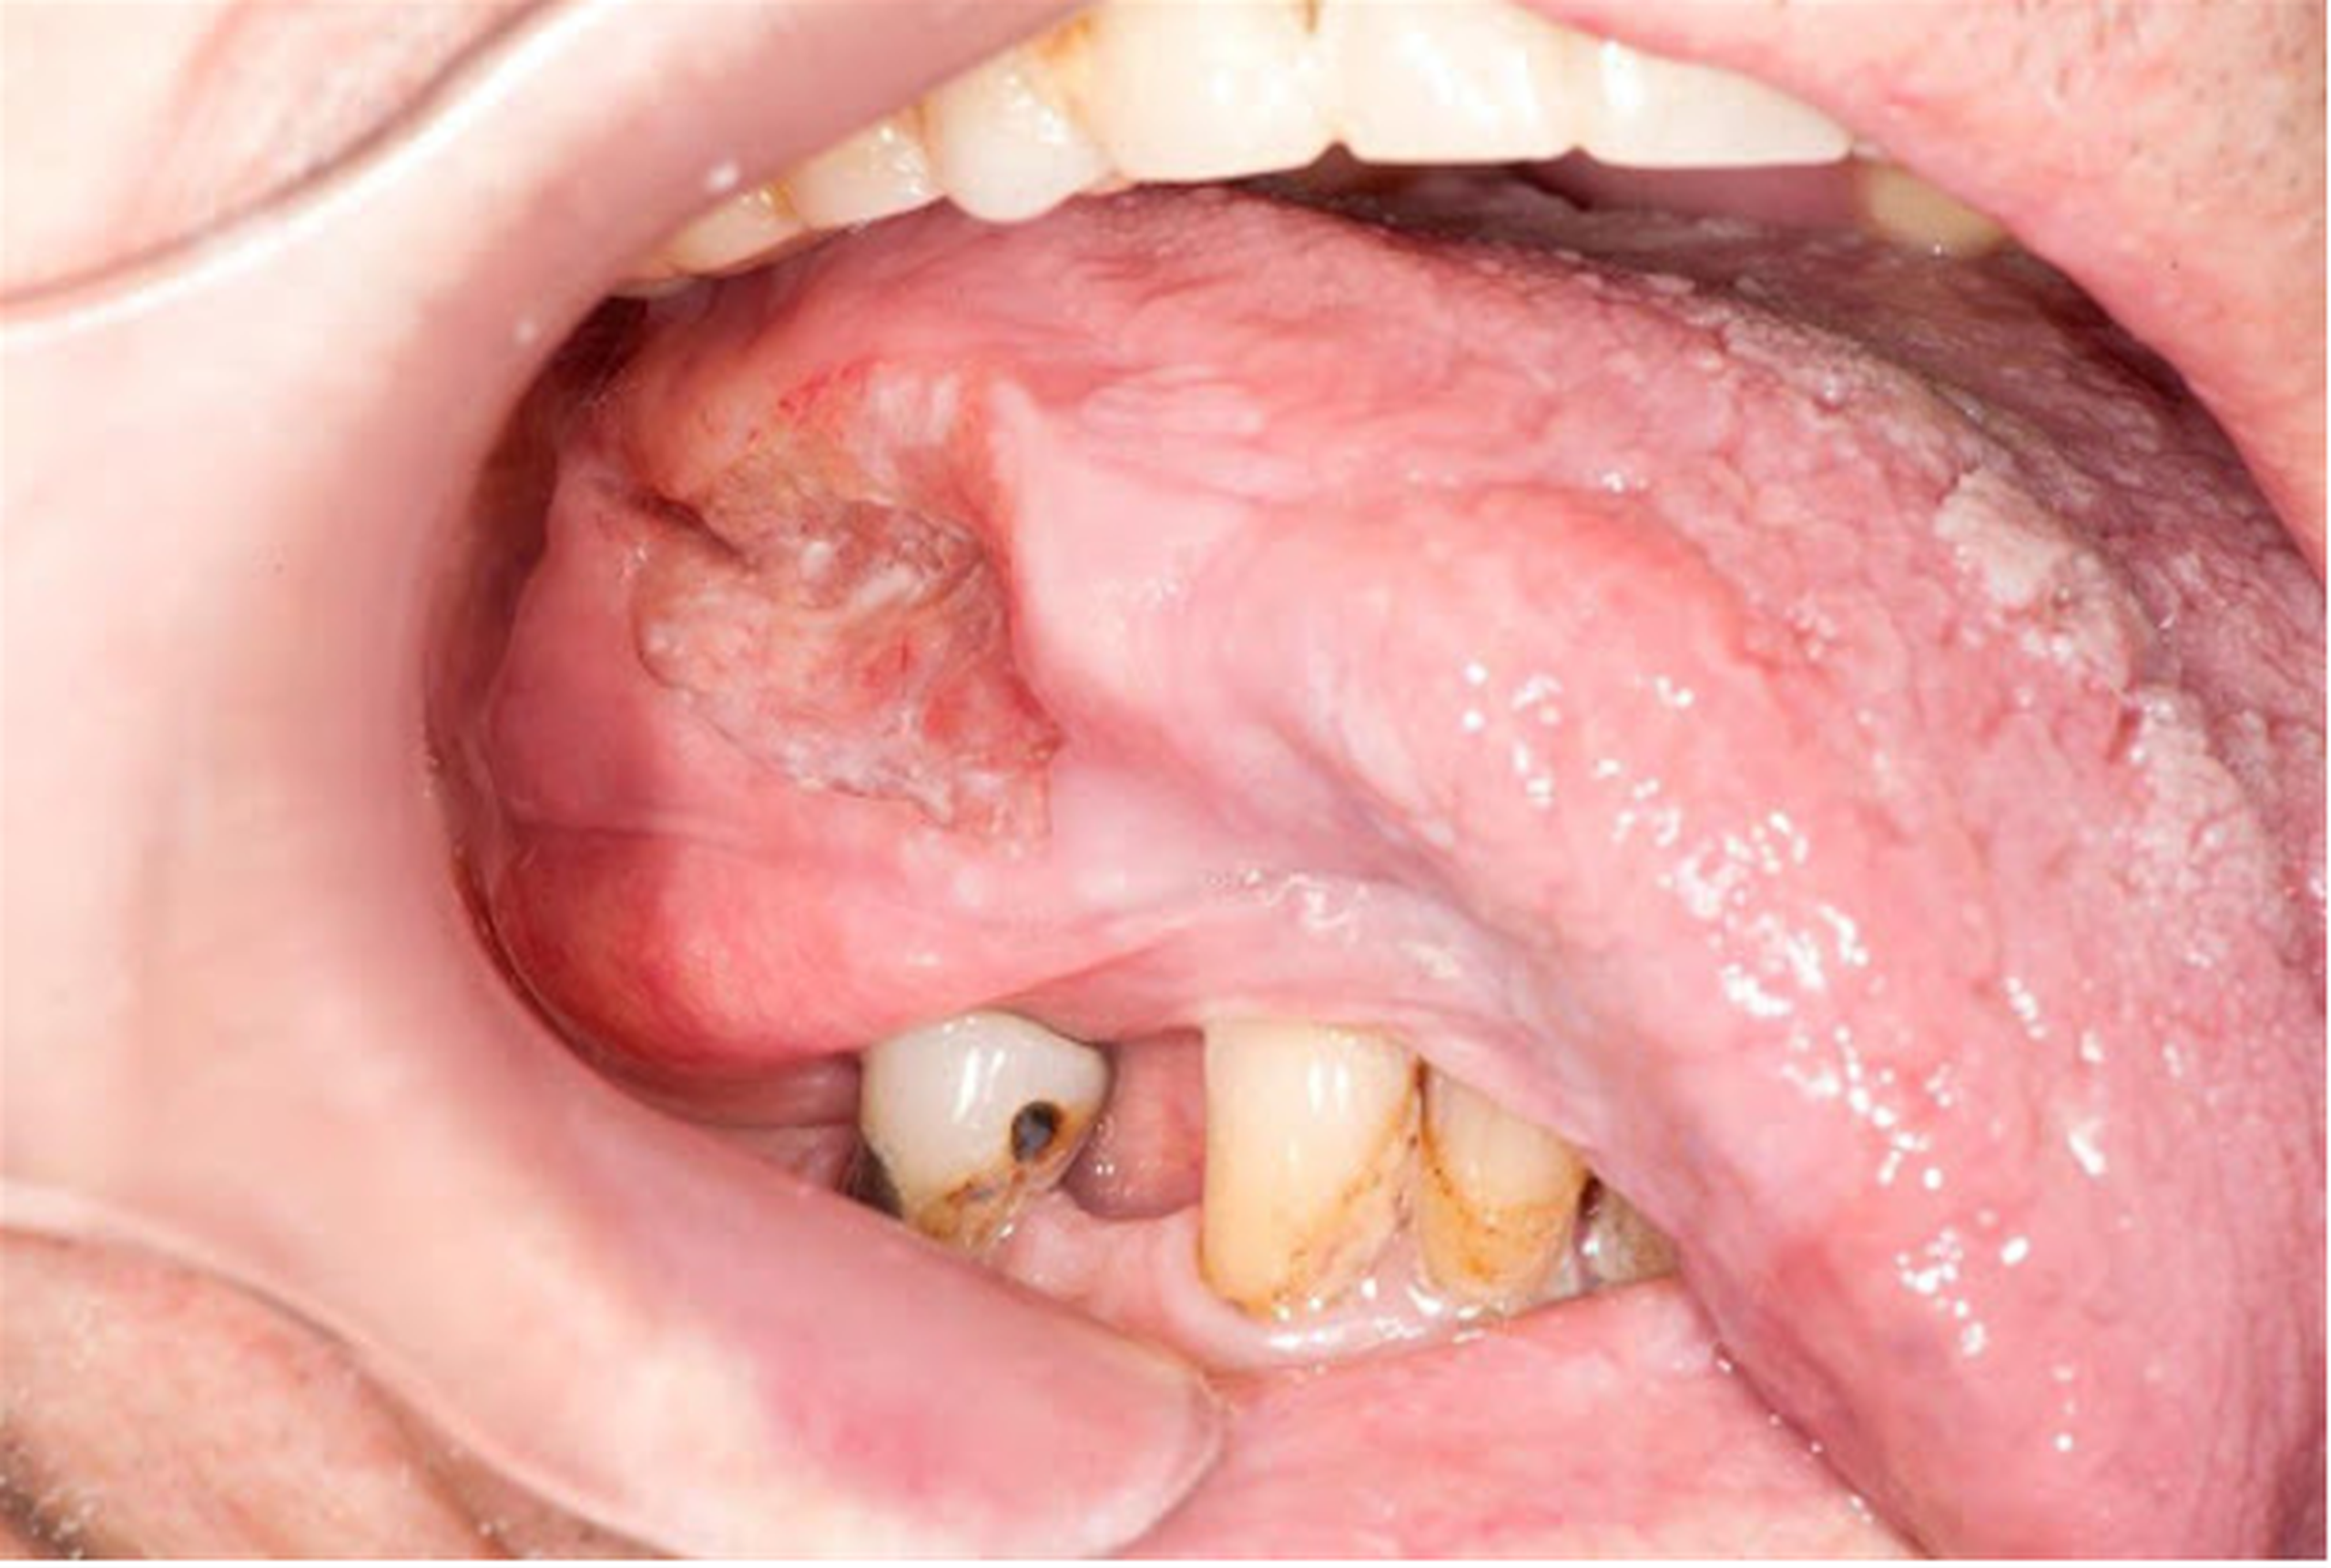

Ung thư miệng xảy ra khi các tế bào tăng sinh và phát triển bất thường trong các mô của miệng hoặc cổ họng. Các tế bào vảy là các tế bào mỏng, phẳng nằm bên trong miệng thường là nơi bắt đầu ung thư miệng. Hút thuốc và uống rượu là những yếu tố nguy cơ chính gây nên gây bệnh. Chúng ta hãy cùng tìm hiểu cụ thể hơn ung thư miệng là gì cũng như những biện pháp phòng tránh qua bài viết sau.

Ung thư miệng thuộc về một nhóm ung thư lớn được gọi là ung thư đầu và cổ, nó là ung thư phát triển trong các mô của miệng hoặc cổ họng. Ung thư biểu mô tế bào vảy là ung thư chiếm đa số trong các loại ung thư miệng. Loại ung thư này bắt đầu từ các tế bào vảy, là những tế bào mỏng, phẳng tạo thành lớp niêm mạc của miệng và cổ họng.

Các triệu chứng của ung thư miệng bao gồm:

Ung thư miệng hình thành khi các tế bào trên môi hoặc trong miệng phát triển những thay đổi (còn gọi là đột biến) trong DNA của chúng. Các đột biến sẽ làm cho các tế bào thay vì chết đi theo chu trình sau khi đã hoàn thành nhiệm vụ thì các tế bào lại tiếp tục phát triển và phân chia mạnh. Các tế bào bất thường tích tụ có thể tạo thành một khối u. Theo thời gian, chúng có thể lan rộng bên trong miệng và lan sang các vùng khác của đầu và cổ hoặc các bộ phận khác của cơ thể.

Hầu hết các bệnh ung thư miệng là ung thư biểu mô tế bào vảy. Tế bào vảy là là những tế bào mỏng, phẳng nằm ở môi và bên trong khoang miệng.